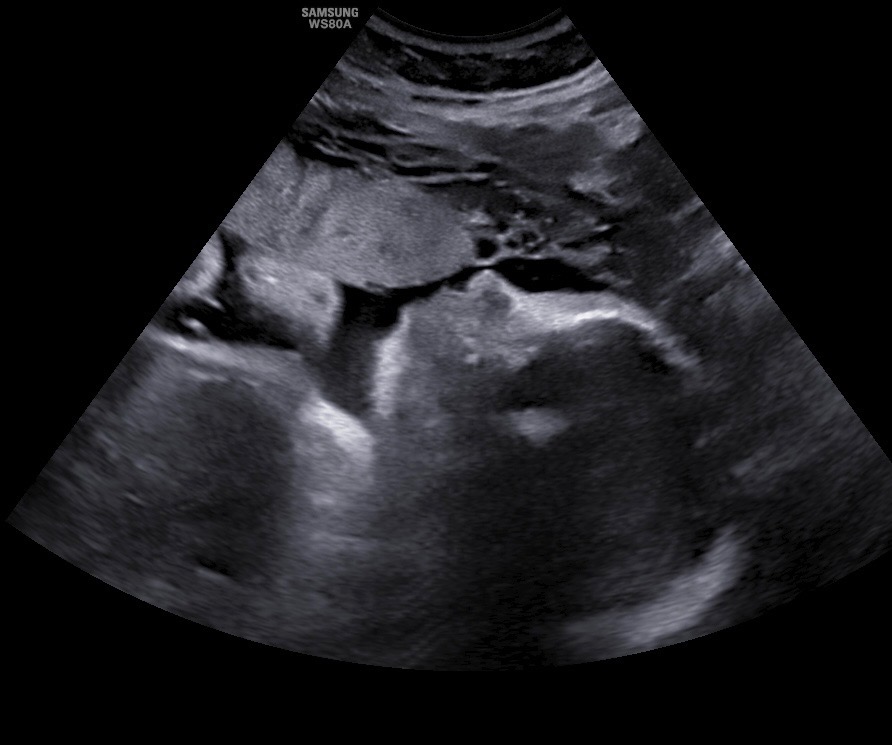

But halfway through this pregnancy, they received devastating news: their daughter, Kennedy, has been diagnosed with a rare and complex congenital heart defect called CCTGA/LTGA — affecting just 1 in 200,000 babies. In addition, Kennedy’s heart has several other serious abnormalities, including:

• VSD (ventricular septal defect)

• Mesocardia

• Ebsteinoid displacement of the tricuspid valve

• Severe tricuspid regurgitation

• Diffuse hypoplasia of the aorta

Doctors have said that on a scale of 1 to 10, Kennedy’s condition is a 10 in complexity and severity. She will require multiple open-heart surgeries, starting just days after birth, and will spend at least two months in the Cardiac Intensive Care Unit (CICU).